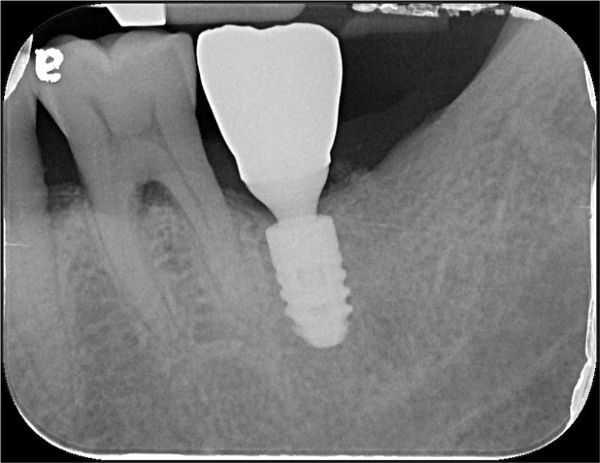

植牙後X光確認

術後X光